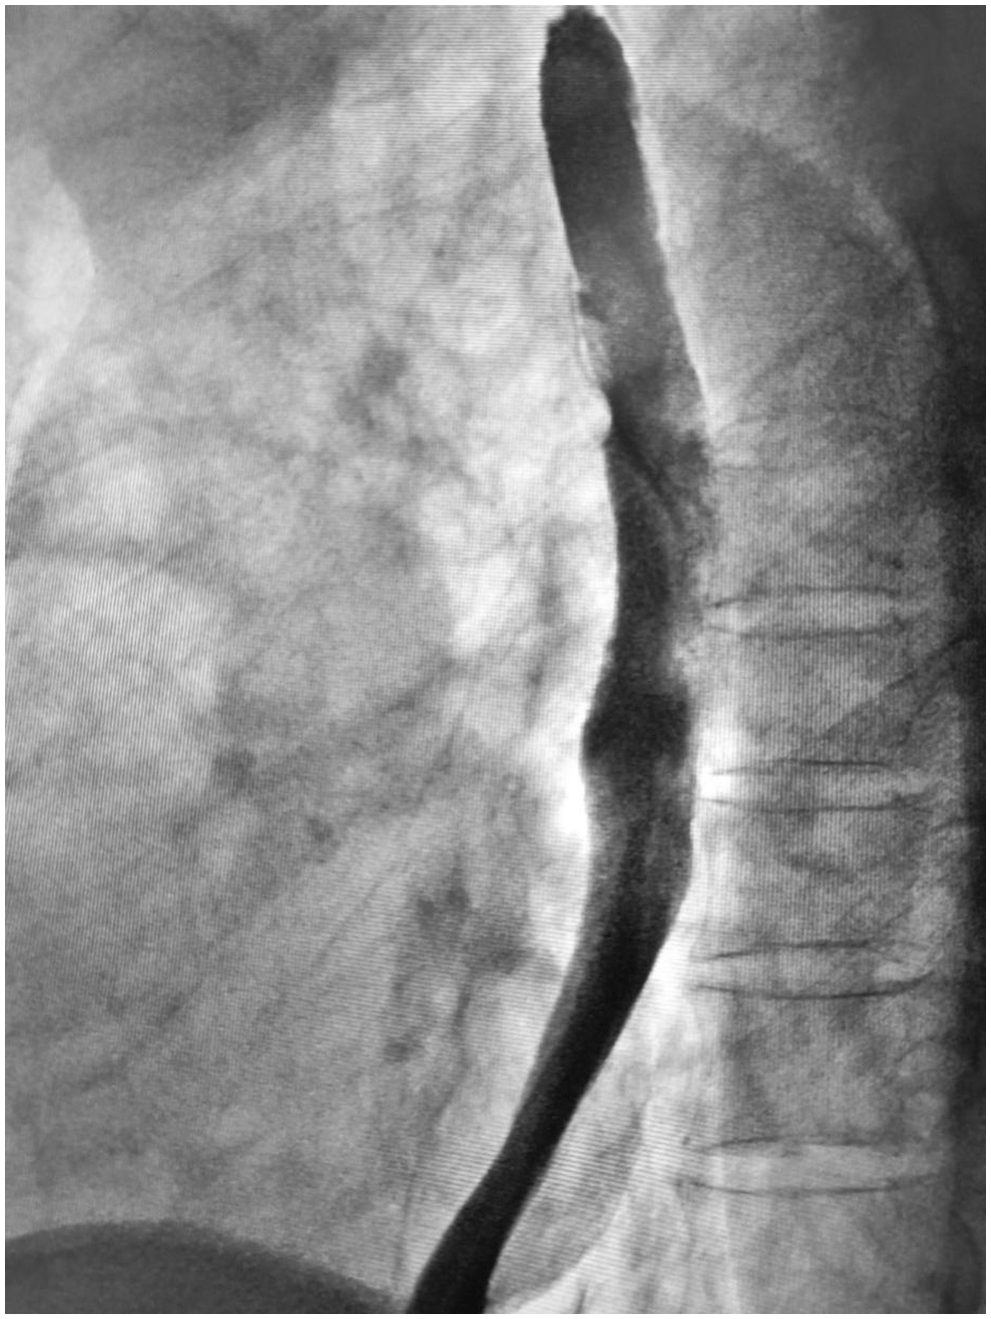

A 65-year-old man was referred to our hospital for investigation of atypical chest tightness of gradual onset over the previous 6 months. He denied weight loss, dysphagia, upper GI bleeding, reflux, or other symptoms. Blood and urine biochemistry showed almost normal results. However, transthoracic echocardiography revealed a solid echoic mass of approximately 16 cm behind the left atrium and significant compression of the left atrium. Chest computed tomography (CT) with contrast administration was performed. The examination was also completed by volume rendering reconstruction (VR) (Fig. 1) and revealed a solid mass of approximately 163 × 73 mm (the volume was 1308.92 mm3) visible behind the left atrium. The heart was compressed forward, the adjacent left atrium was significantly compressed, and the adjacent bronchi and esophagus were significantly compressed and displaced. A barium swallow study revealed that the lower esophagus was clearly shifted to the left under pressure, partially shifted forward in the left anterior oblique position, and shifted backward in the right anterior oblique position (Fig. 2). The barium meal passed smoothly. Considering that the patient had severe cardiac symptoms, thoracotomy was performed emergently. During the operation, the tumor was found to be approximately 17 cm in diameter and located in the posterior mediastinum, with unclear boundaries in some areas, abundant blood vessels on the surface, and cystic firmness in texture. The tumor was punctured with a thick needle to extract the internal fluid, which was bloody and mixed with sediment. After suction, the cyst wall was sutured and used for traction. The tumor wall was free along the edge of the tumor, with obvious oozing but no obvious blood-supplying artery. Because the source of the tumor was not known before the operation, the operation was very difficult. Further exploration on a subbase revealed that the tumor originated in the esophagus and had a short, wide pedicle on the lateral wall of the esophagus. Although the origin of the tumor has been clarified thus far, it is still difficult to completely remove the tumor. Fortunately, the entire tumor was finally removed with difficulty from meticulous operation. Postoperative pathological examination showed that the tumor was grayish yellow in section, had cystic firmness, was soft in quality and yellowish and sticky and frozen in appearance; part of the gray matter was broken, and part of the envelope was yellowish dark red. The diagnosis was an esophageal gastrointestinal stromal tumor with nuclear division <5/50 HPF (Fig. 3). The tumor basal margins were negative, and lymph node examination showed no cancer metastasis. Immunohistochemical indicators were as follows: SMA (−), S-100 (−), actin (+), desmin (−), PCK (−), EMA (−), VIM (+), CD34 (+), c-kit (+), Dog-1 (+), MDM-2 (+), CDK4 (−), and KI67 (+4%). After a multidisciplinary meeting, the patient received adjuvant therapy. Through multidisciplinary consultation, the patient received oral treatment with 400 mg of imatinib once daily after the operation and was closely followed up with chest CT scans (Fig. 4) or the barium esophagram every 6 months. After 3 years, the patient showed no sign of local recurrence with regular barium esophagram (Fig. 5), and no abnormally enlarged lymph nodes shadows were found on CT scans of the chest and abdomen performed during the follow-up.

Figure 5: Barium esophagram showed no signs of local recurrence at the three-year follow-up

Finally, molecularly targeted therapy has revolutionized the treatment of GISTs and facilitated scientific research on GISTs. Activating mutations of KIT or platelet-derived growth factor receptor alpha (PDGFRA) are found in the majority of GISTs [14]. Imatinib, as a first-line standard therapy for recurrent or metastatic GISTs, has proven clinical benefit in patients, and the standard dosage is 400 mg/day [15]. Unfortunately, it has been reported that more than half of patients develop resistance to imatinib after approximately 2 years, resulting in fatal disease progression [14,15]. Resistance to imatinib can include primary and secondary resistance; hence, mutation testing is recommended when imatinib is being considered for treatment. Other structural inhibitors have been developed, and sunitinib and regorafenib are multitarget inhibitors that inhibit KIT, platelet-derived growth factor receptors, vascular endothelial growth factor receptors and so on [16]. Sunitinib was initially approved for imatinib-resistant disease, and regorafenib was mainly used for imatinib-or sunitinib-resistant GIST with a 3-week-on/1-week-off regimen [17]. In the case presented here, imatinib therapy was used immediately postoperatively. Fortunately, the patient had a pathological response to imatinib treatment (400 mg/day) after resection and has been on the drug ever since. The patient’s postoperative chest CT examination showed that there was no shadow at the original mass-occupying site. On the imaging results, all lesions disappeared, and no signs of metastasis were observed in the esophagus and chest.